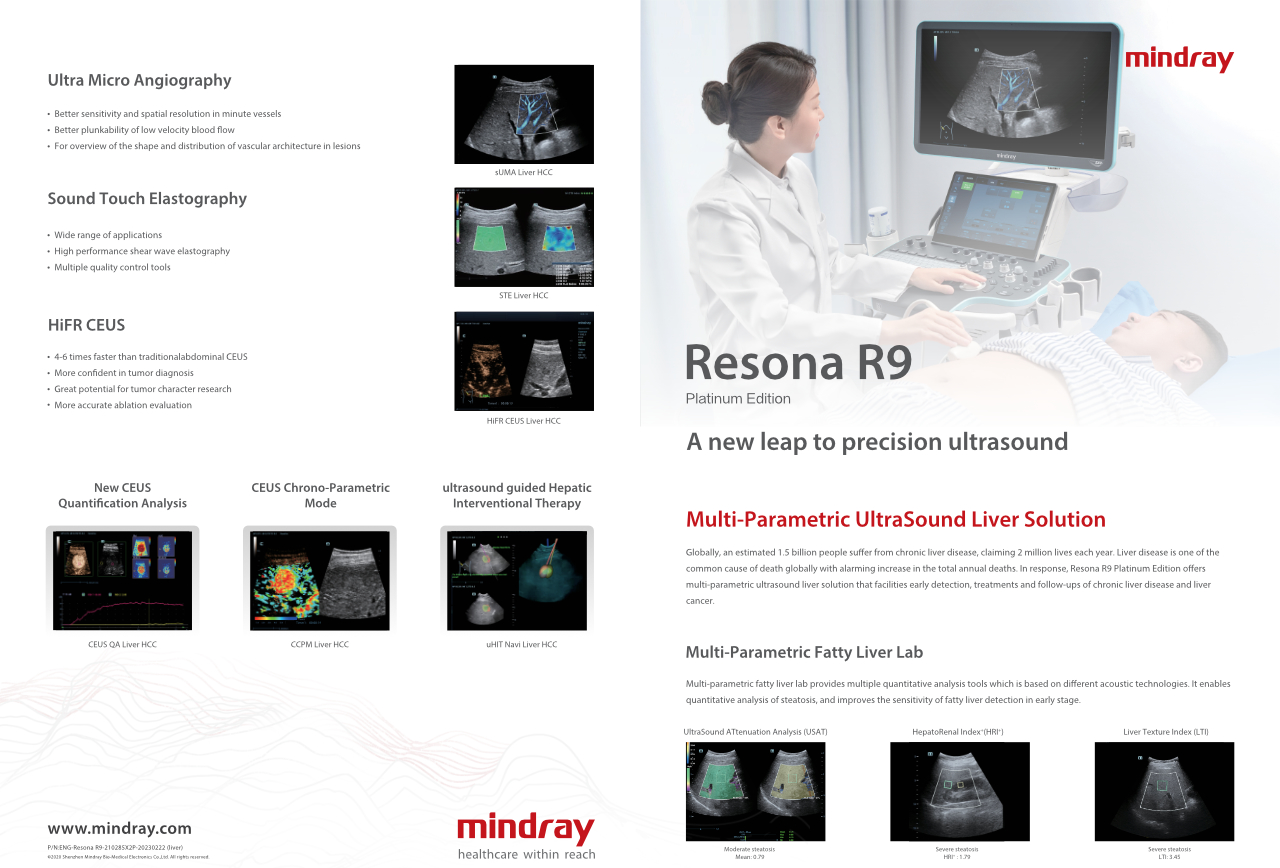

Resona R9 Platinum Edition

Een sprong vooruit in precisie-echografie

De Resona R9 Platinum Edition integreert een verscheidenheid aan innovatieve multi-parametrische tools met een nieuw niveau van beeldhelderheid, en maakt hiermee weer een sprong voorwaarts zowel voor klinische routine als voor onderzoeksdoeleinden.

Wereldwijd lijden naar schatting 1,5 miljard mensen aan een chronische leveraandoening, die elk jaar aan 2 miljoen mensen het leven kost. Leveraandoeningen zijn wereldwijd een van de meest voorkomende doodsoorzaken met een alarmerende toename van het totale aantal sterfgevallen per jaar. Als antwoord hierop biedt Resona R9 Platinum Edition een oplossing voor multi-parametrische leverechografie die vroege opsporing, behandeling en follow-ups van chronische leveraandoeningen en leverkanker mogelijk maakt.